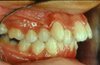

ÜST İLERİ İTİM

Üst dişler, alt dişlerin ilerisinde ya da alt dişler geridedir. Fonksiyon ve estetik bozulmuştur.